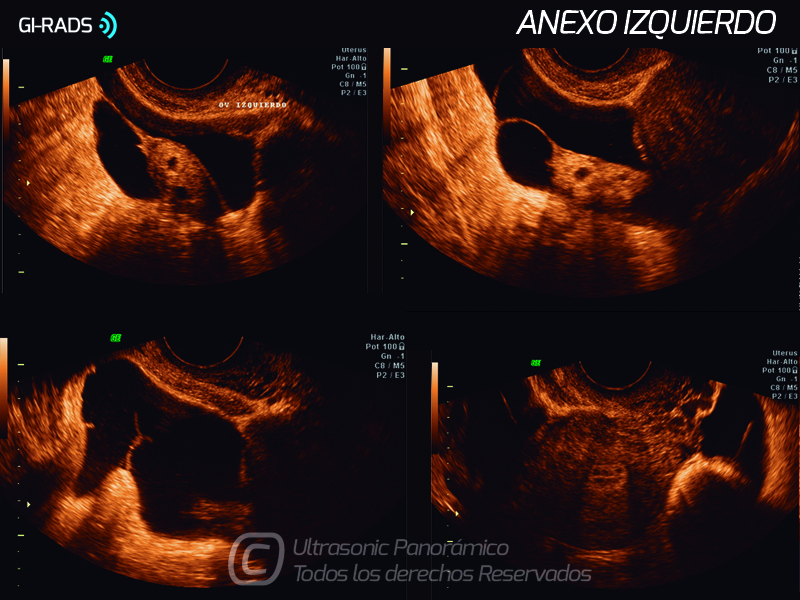

Patologías Benignas – Pseudoquiste de Inclusión Peritoneal

• Patologías Benignas – Pseudoquiste de Inclusión Peritoneal